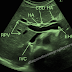

A well-defined echogenic focus measuring 4.0 mm calculus is noted, showing posterior acoustic shadowing.

Pelvicalyceal system is not dilated.

No evidence of hydronephrosis or focal mass lesion is seen.

Hepatomegaly noted.

Bilateral renal calculi (nephrolithiasis) seen with echogenic foci showing posterior acoustic shadowing.

No obvious hydronephrosis / obstructive uropathy detected (if applicable).

The findings demonstrate an enlarged liver consistent with hepatomegaly,

along with the presence of calculi in both kidneys (bilateral renal calculi).

The renal stones may vary in size and location, with possible posterior acoustic shadowing.

Ultrasonography provides a non-invasive and effective modality for evaluating liver size and renal stone disease.